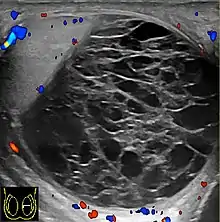

Hemoscrotum can follow trauma (such as a straddle injury) or can be a complication of surgery. It is often accompanied by testicular pain. It has been reported in patients with hemophilia and following catheterization of the femoral artery. If the diagnosis is not clinically evident, transillumination (with a penlight against the scrotum) will show a non-translucent fluid inside the scrotum. Ultrasound imaging may also be useful in confirming the diagnosis. In severe or non-resolving cases, surgical incision and drainage may be required. To prevent recurrence following surgical drainage, a drain may be left at the surgical site.

Current research is ongoing for proper diagnosis and helping to differentiate among other conditions. Doppler ultrasound in a retrospective study was shown to be helpful for differential diagnosis of patients with acute scrotum.[13] Accuracy of imaging studies is higher for the differential diagnosis of testicular torsion and epididmo-orchitis, which there can still be the possibility of misdiagnosis for hematoceles due to testicular torsion.[13] Further research in this area shows importance for surgical decision making in hematoceles.[13]